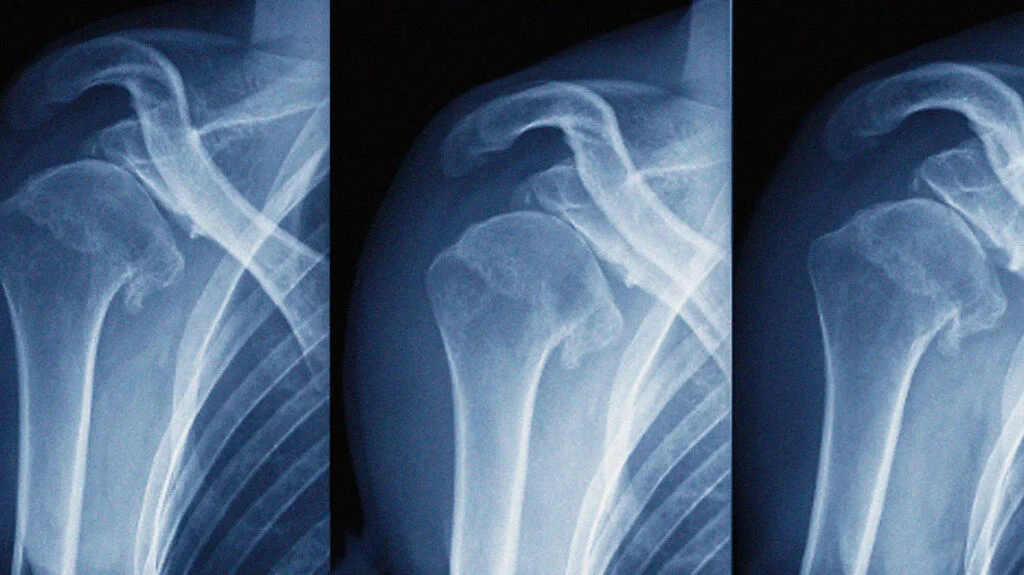

Sai khớp là gì? Những điều cần biết về sai khớp